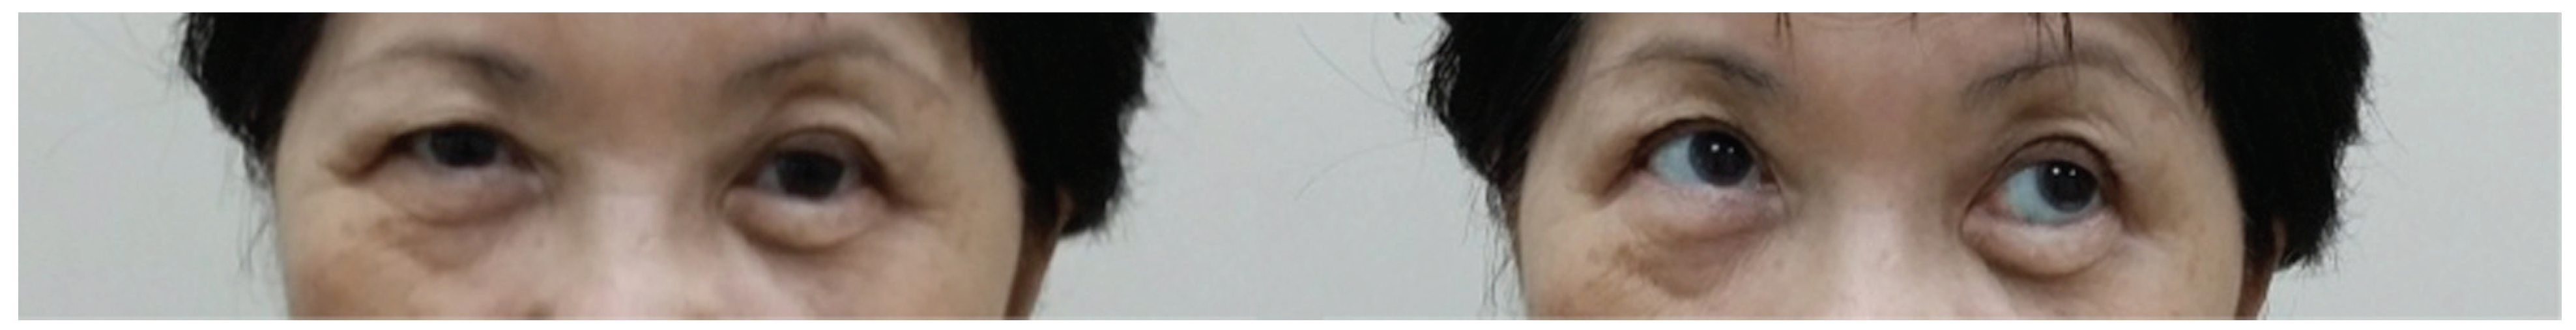

A 66-year-old woman sustained a left ZMC fracture and orbital floor fracture following a fall (Figure 5), resulting in left enophthalmos and diplopia on upward gaze. She underwent ORIF and orbital floor reconstruction 12 days after the injury. Both the 0.4-mm titanium orbital mesh and orbital rim plate were used (Figure 6). Postoperatively, she complained of progressive worsening of left upward gaze diplopia, starting around 2 weeks postoperatively and worsening over 4 weeks. There was also dimpling noted over the left lower lid due to lid retraction; however, forced-duction test was negative. She was given lower eyelid scar massage, which was performed in an upward oblique fashion from medial to lateral, and steroid injections (8 IU of triamcinolone) into the lower eyelid. On the 9th week postoperative follow-up, she reported improvement of diplopia but still had lower eyelid retraction and a tugging sensation (Figure 7). She was then given 0.3 mL of hyaluronic acid (HA) filler (Restylane; Galderma, Lausanne, Switzerland) into the posterior lamella space to correct the lower eyelid retraction. She experienced immediate and sustained (at 1 month) relief of symptoms of tugging and eyelid retraction.

Figure 5. Coronal and sagittal cuts of the CT scan of the face (Case 2) demonstrating the presence of a large left orbital floor defect (arrows).